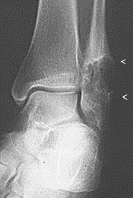

Osteoarthritis